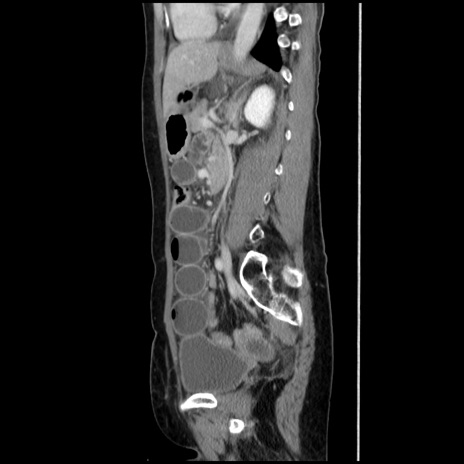

横断像

【症例】40歳代 女性

【主訴】上腹部痛、嘔気・嘔吐

【現病歴】約9時間前頃から急に上腹部痛、嘔気、嘔吐が出現。改善しないため救急要請。

【既往歴】子宮頚癌(広汎子宮全摘術、放射線療法)、腸閉塞

【身体所見】腹部:平坦、軟、腸雑音亢進、上腹部を中心に腹部全体に圧痛あり。

【データ】WBC 8400、CRP 0.03